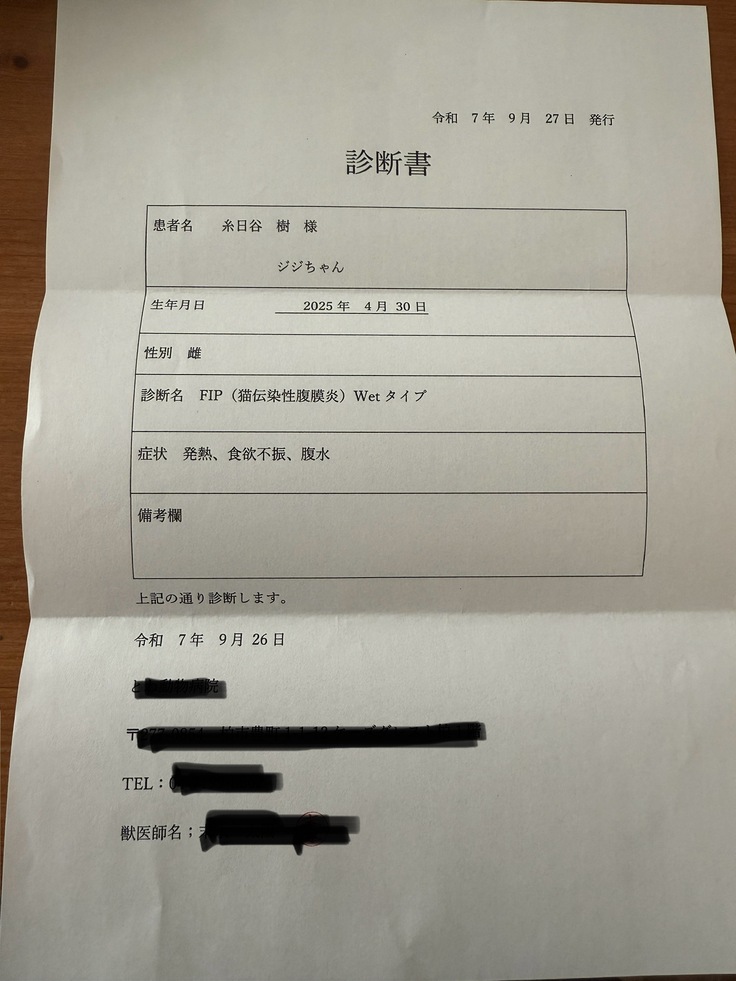

この日に初めて猫伝染性腹膜炎(FIP)かもしれないという話をされました。

致死率が高いこと、月齢が浅いため重症化しやすいこと、どこの病院でも治療ができるわけではないこと。

そして詳細の検査の結果、9/26、正式にFIP(Wetタイプ)と診断を受けました。